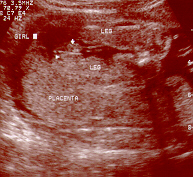

It's a Girl!!